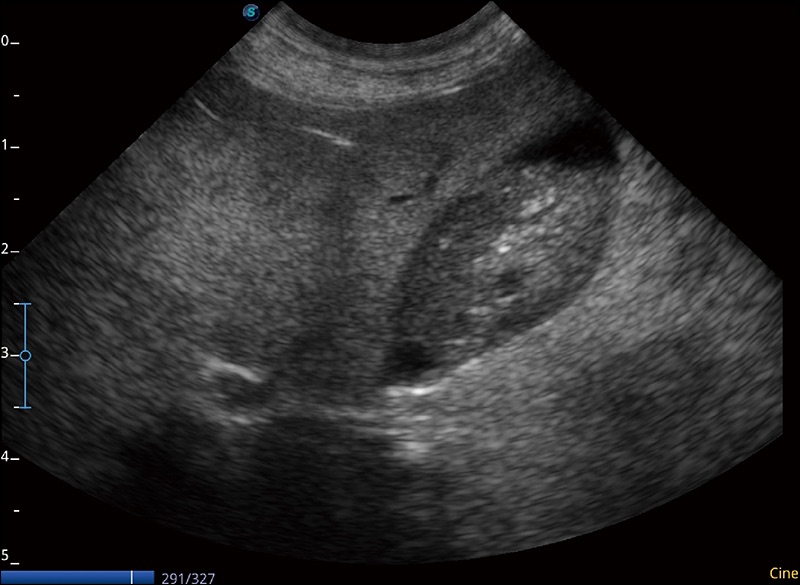

连续波多普勒成像CW

为心脏功能评估提供更多诊断信息